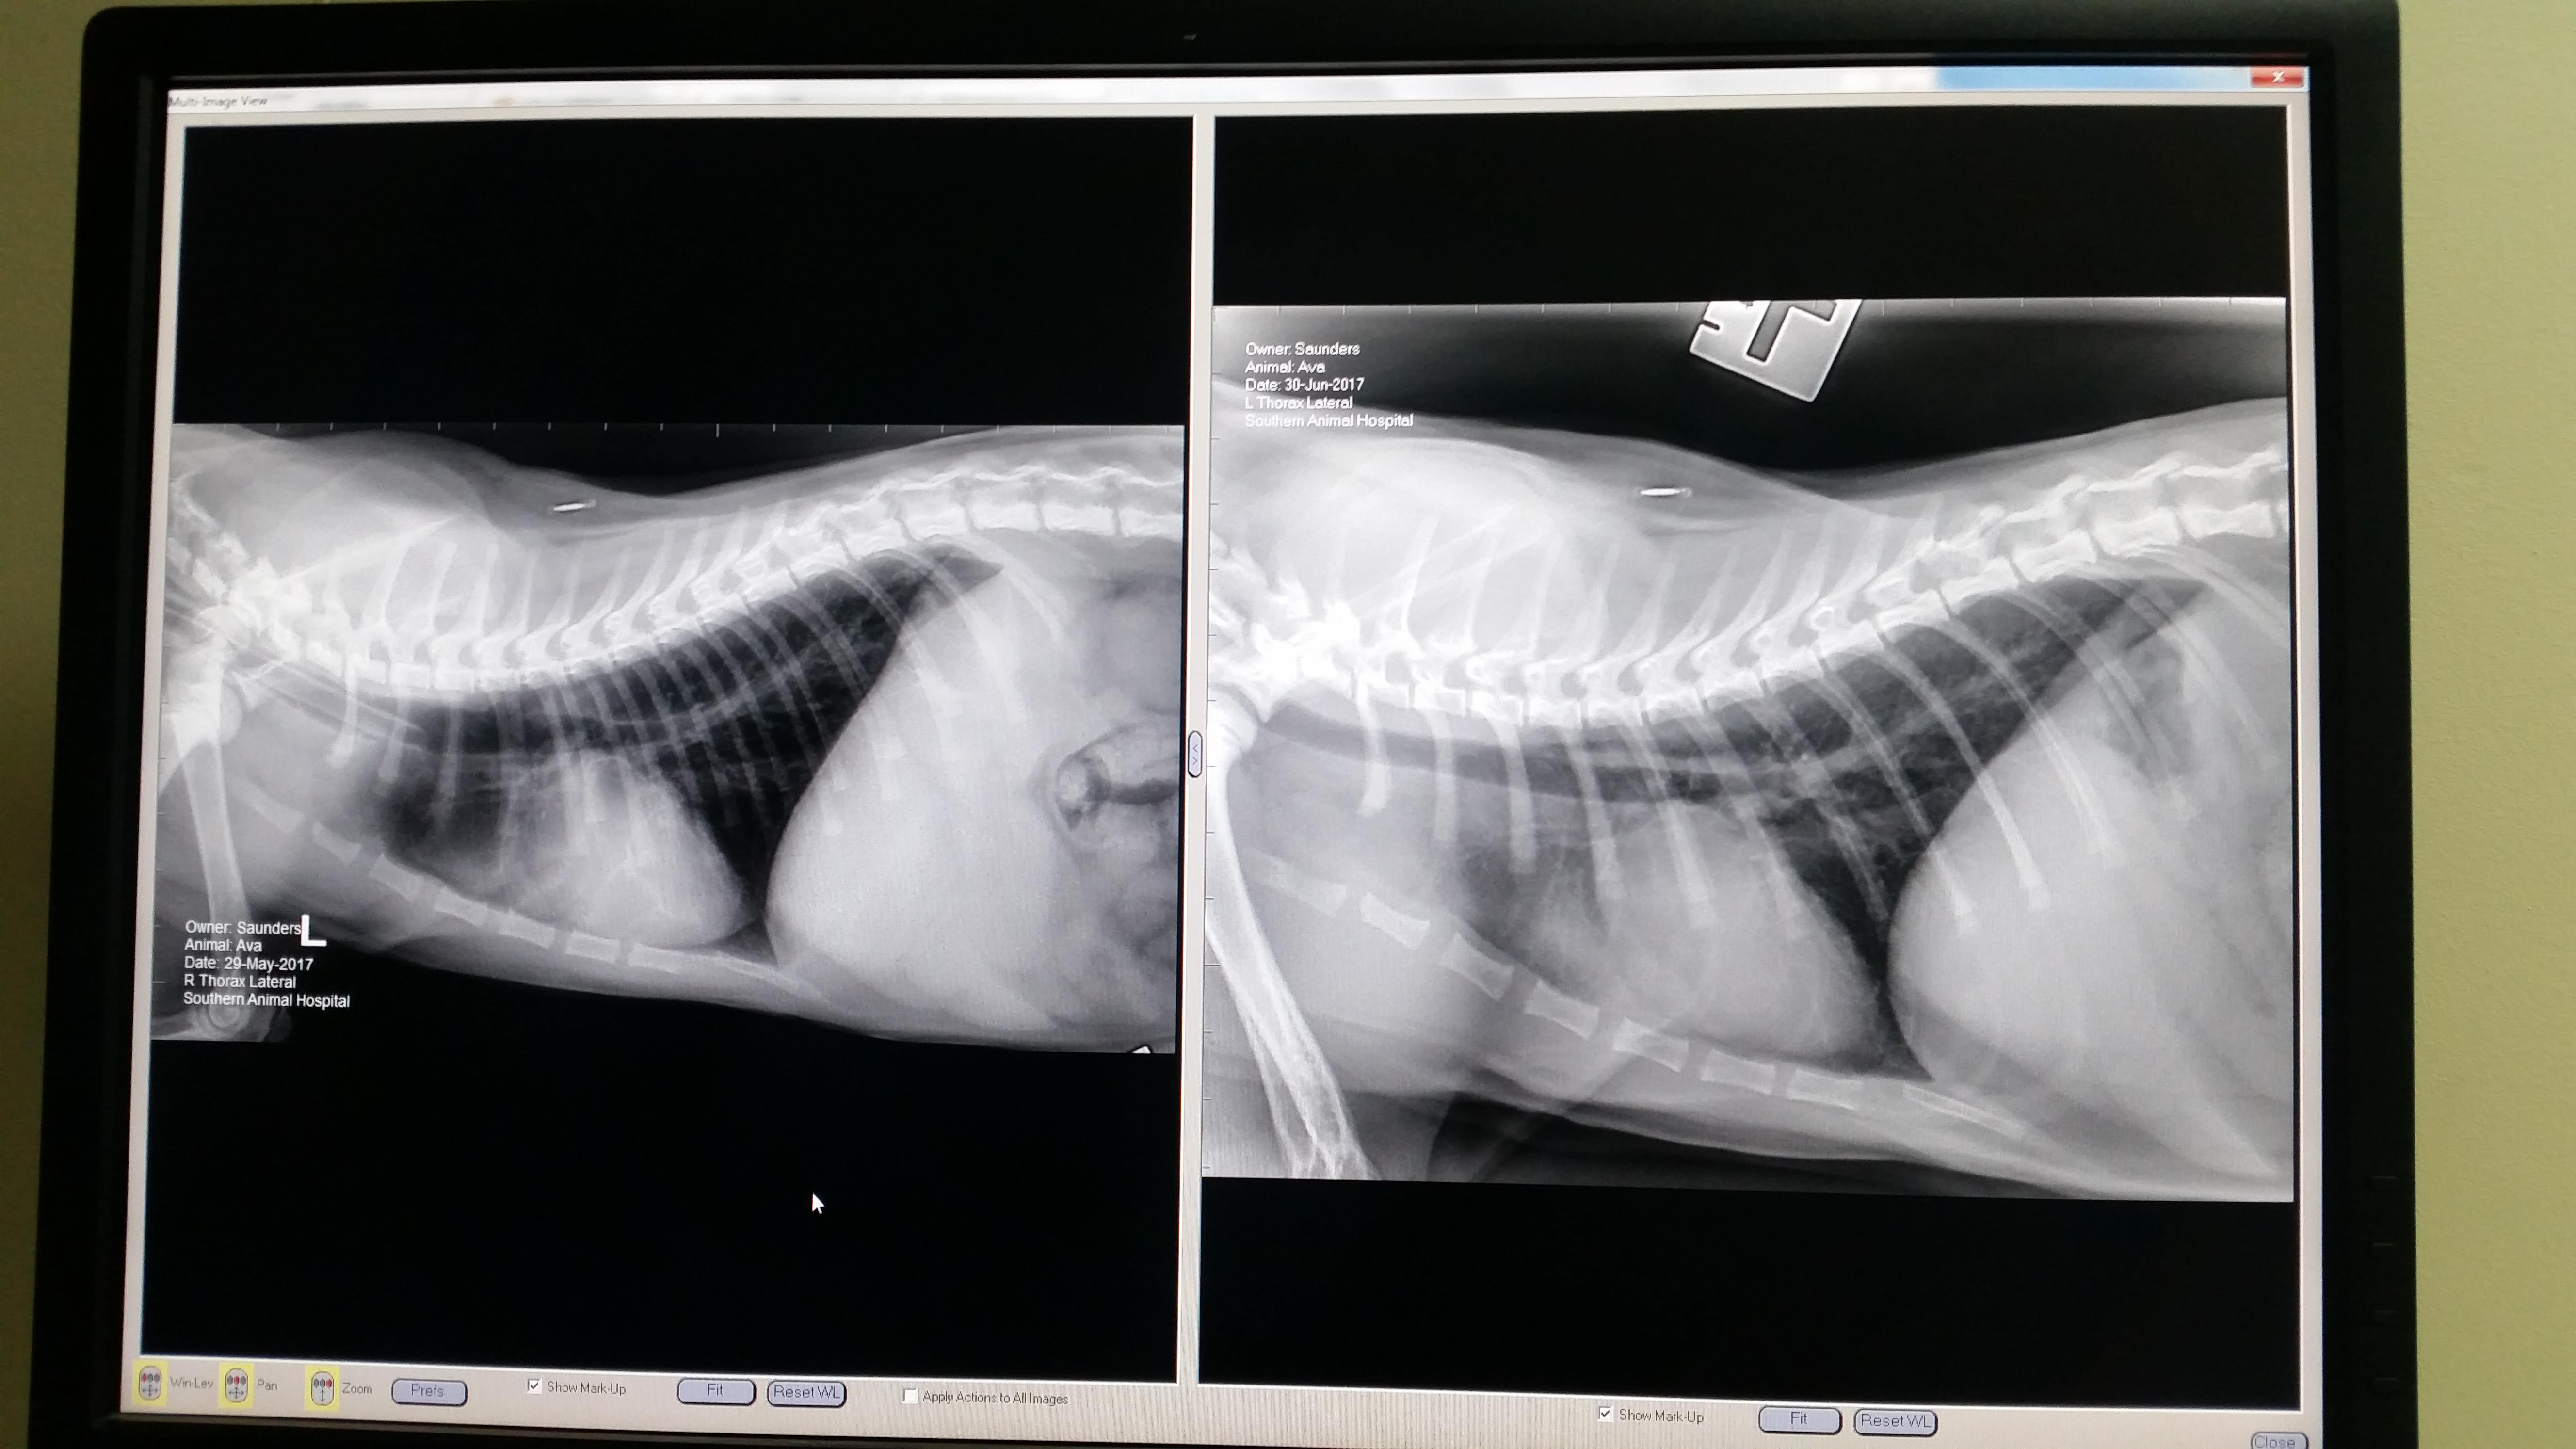

Hi so my Kitten was coughing so I took her to the vet we got xrays on the 29th of may and it showed an area of white that should be black so she was put on a course of antibiotics for a month and we got xrays again on the 30th of june and the white area had gotten bigger. My vet is unsure what it is and as she is only 5 months old she is too small to do the test with the tube/camera down the throat so waiting for her to get big and on antibiotics again. Do you have any ideas of what it is?

Poor Ava! I can see that the white area has gotten larger over the past month, despite her antibiotic treatment. Given the location of the larger white area, an aspiration pneumonia would be my primary suspicion, and this typically occurs if an animal vomits and then inhales some of the contents. It is possible that any infection is resistant to the antibiotic being used. Even though she is still too small for endoscopy, it may be worth asking your vet if it is possible to perform an endotracheal wash to obtain a sample of this matter for cytology and culture. Other possible causes of this radiographic change include infectious conditions (such as FIP) or cancer (unlikely given her young age). I hope that all goes well for Ava!